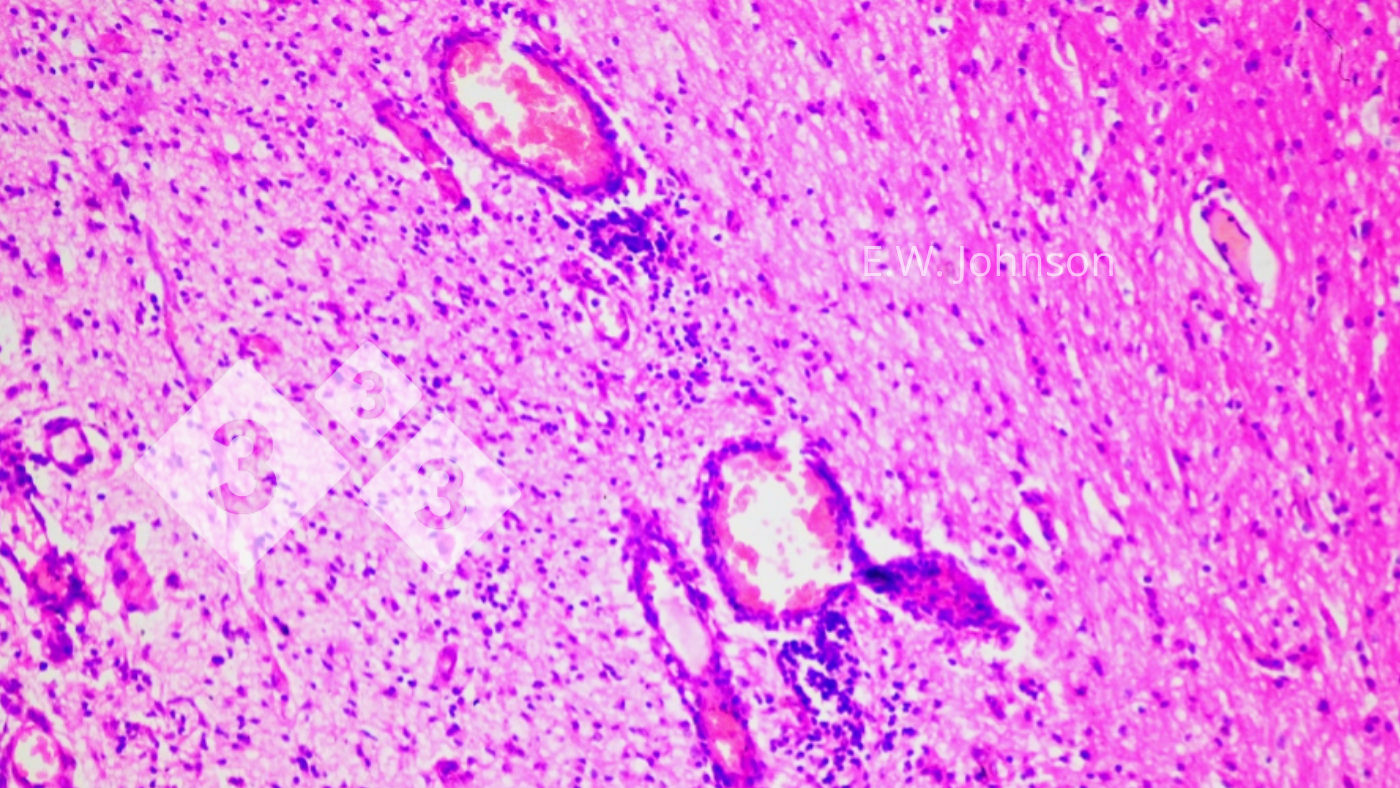

O exame microscópico do cérebro revela meningoencefalite com manguito perivascular e gliose (imagem 2) e infiltração das meninges com células inflamatórias mononucleares e polimorfonucleares mistas (imagem 3).